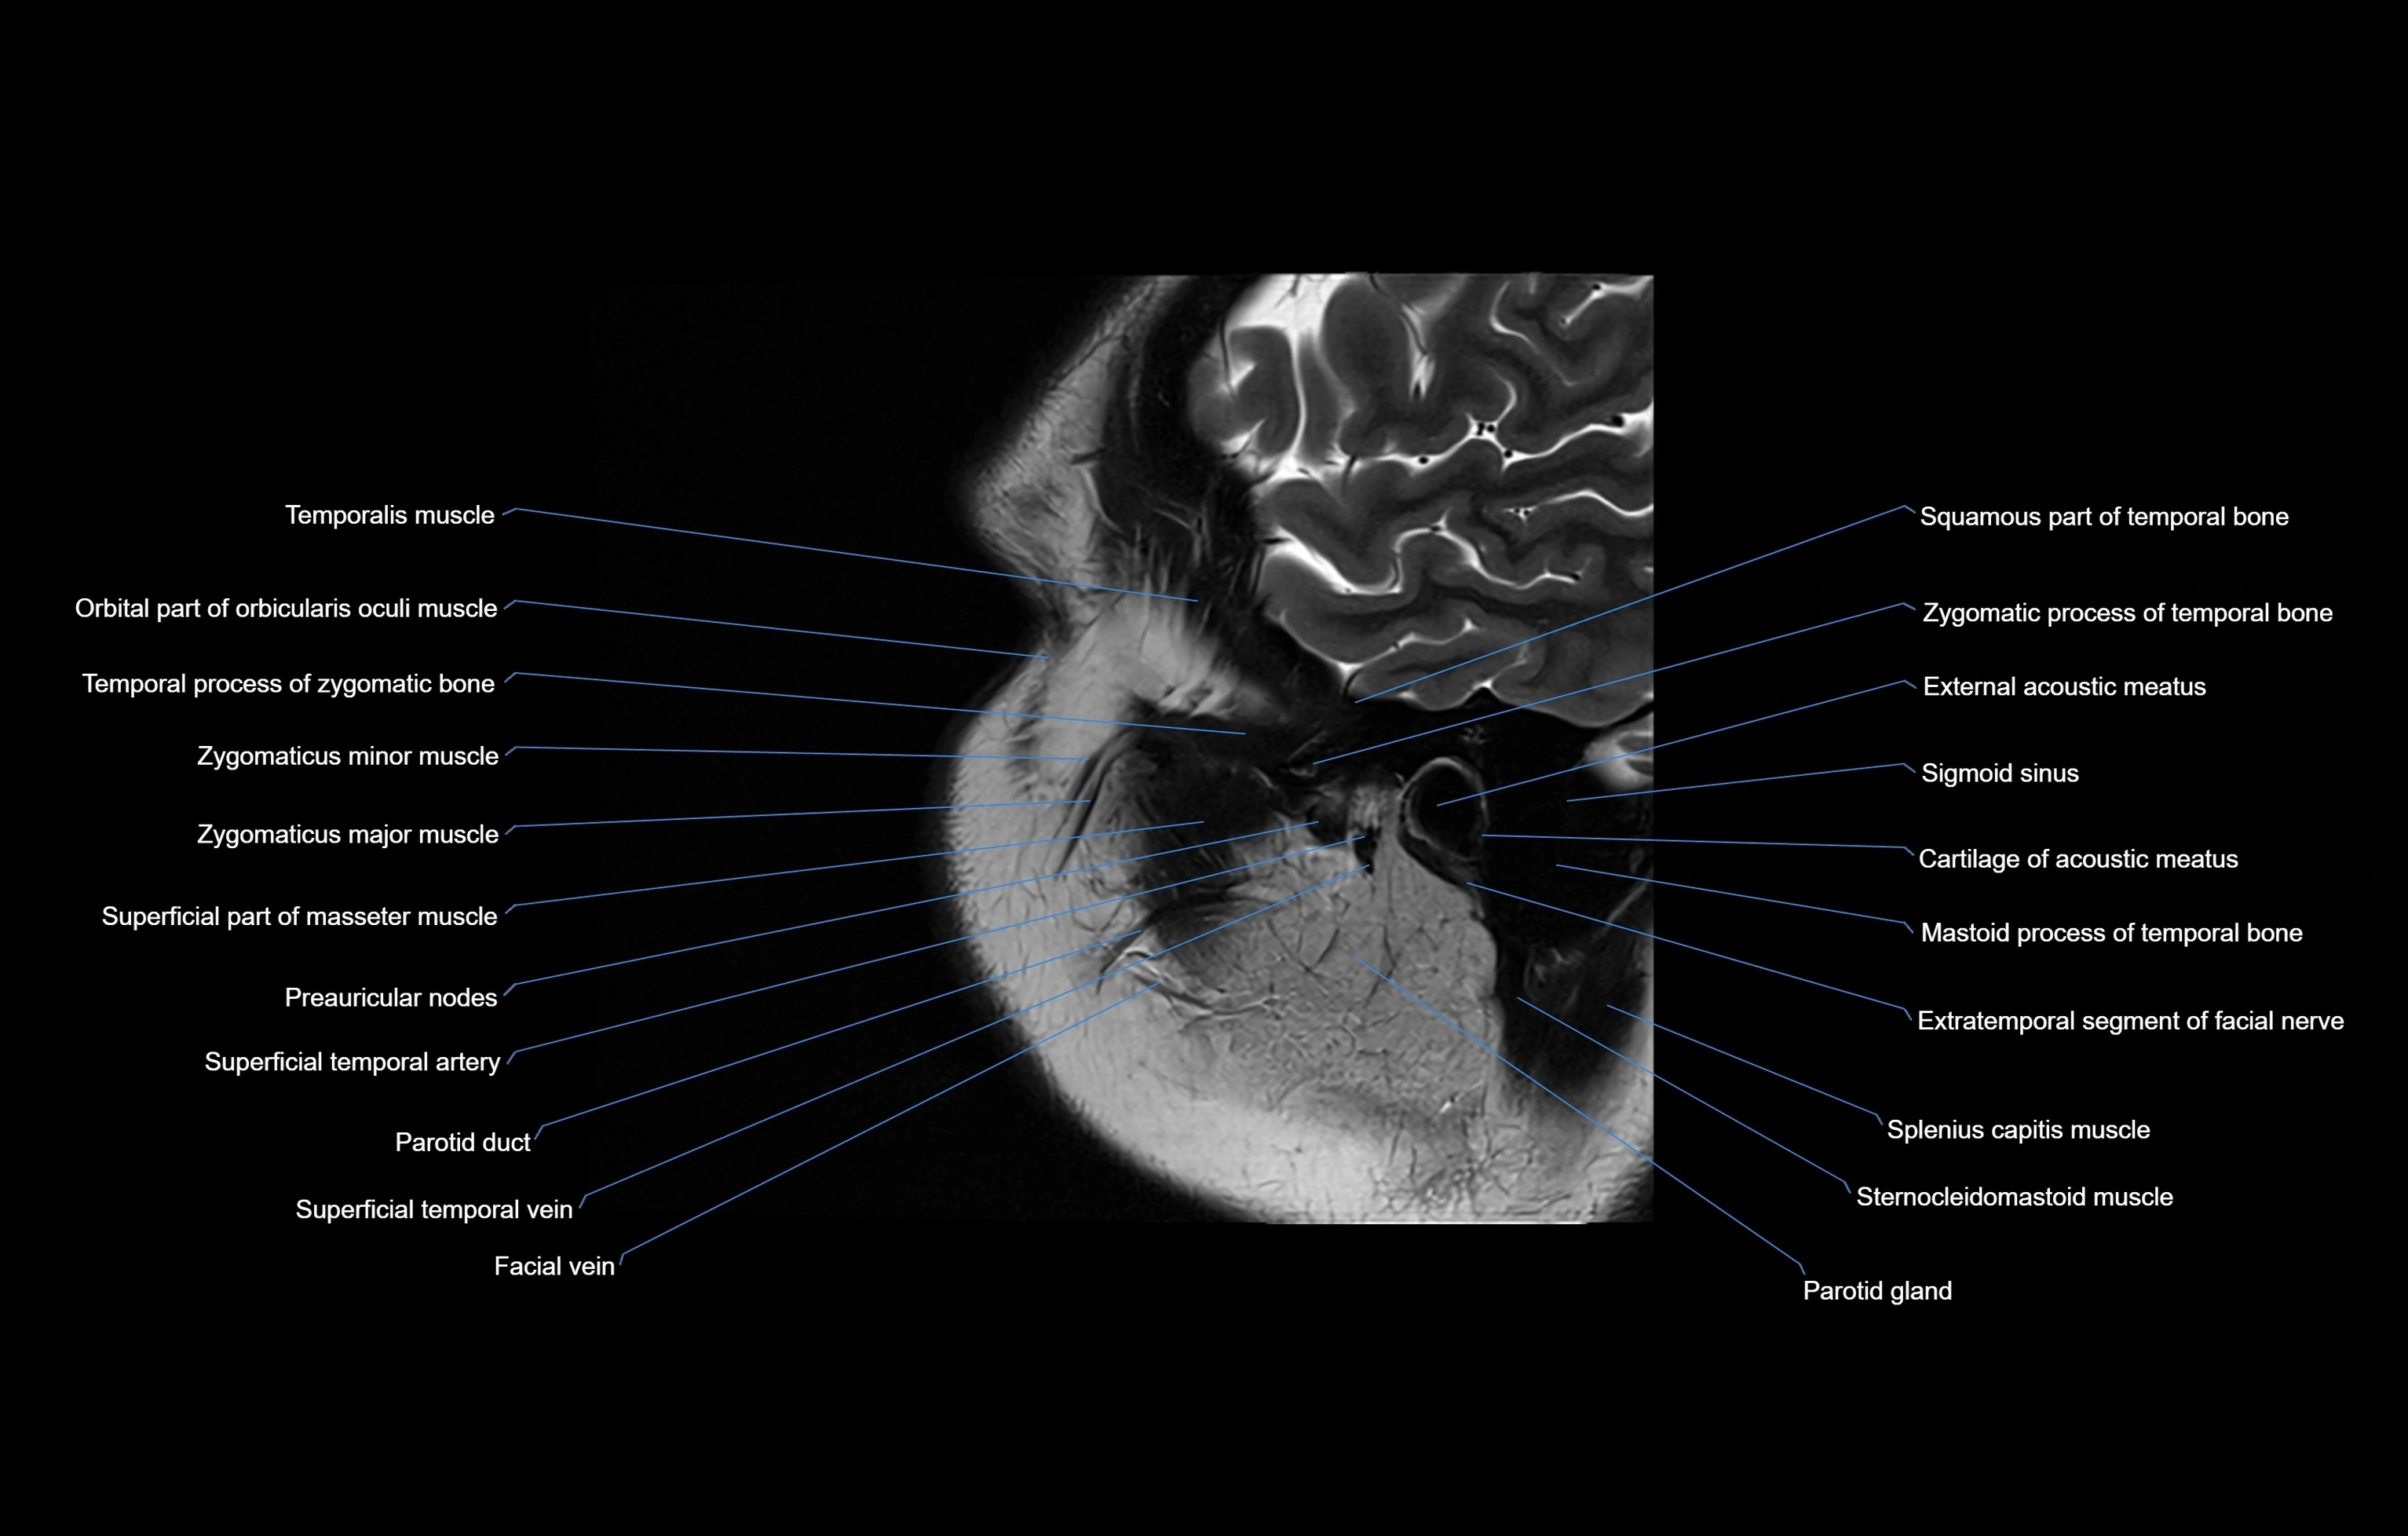

MRI images